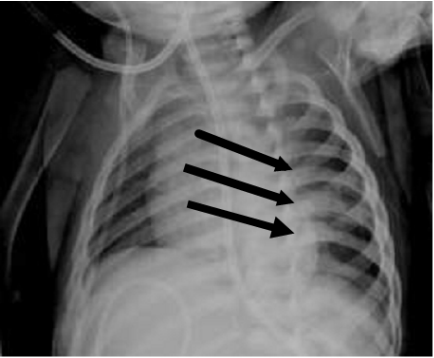

74.一歲女童因呼吸窘迫入院,胸部X光(附圖)意外發現如箭頭所指的病灶顯示後側肋骨有骨痂形 成(callous formation),下列敘述何者正確?

(A)必須排除肺結核的可能 (B)這極有可能是兒虐的結果 (C)肋骨與脊柱的關節脫臼 (D)需手術處理